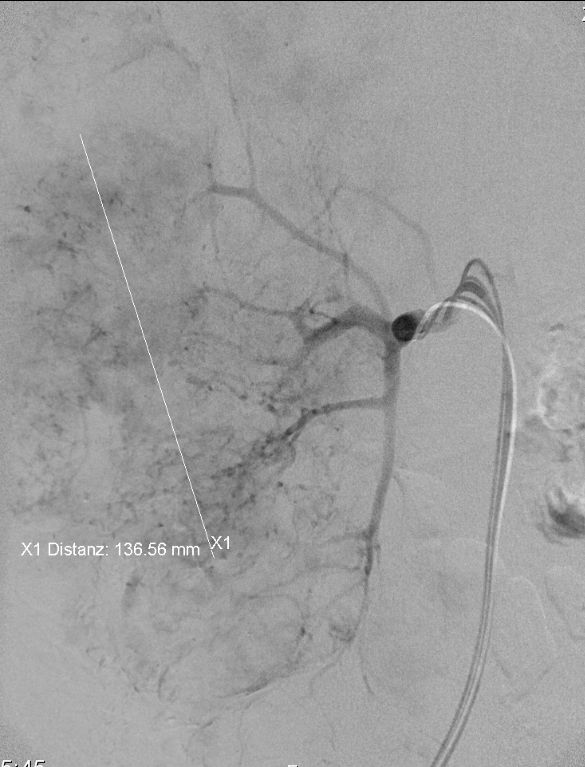

Im CT war der Tumor durch die multiplen Zysten verdeckt. In der DSA ist das atypische Gefäßbild des Nierenzellkarzinoms erkennbar.